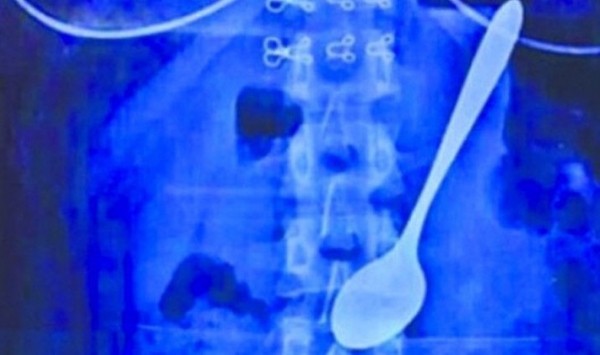

قالت مصادر صينية أن الأطباء نجحوا في استخراج ملعقة طولها 14 سم من معدة طالبة جامعية كانت قد ابتلتعتها في وقت سابق .

و ذكرت المصادر أن طالبة جامعة صينية من مدينة ووهان في مقاطعة خوباي دخلت المستشفى بعد أن ابتلعت بالصدفة ملعقة معدنية طولها 14 سنتيمترا.و

كانت هذه الشابة تأكل بملعقة من كأس مملوءة بالآيسكريم وهي في طريقها إلى السكن الطلابي، وفي هذا الوقت دفعها أحد الطلاب من الخلف عندما كانت الملعقة في فمها ، الأمر الذي جعلها تبتلع الملعقة مع الآيسكريم من دون إرادتها.

و انتشل الأطباء الملعقة من معدة الطالبة بنجاح حيث لم تستغرق العملية أكثر من عشر دقائق دون أن تسبب أي إصابات داخلية.